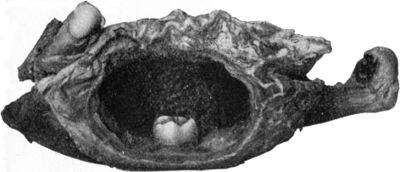

12.Os Innominatum showing new Socket formed after Old-standing Dislocation41